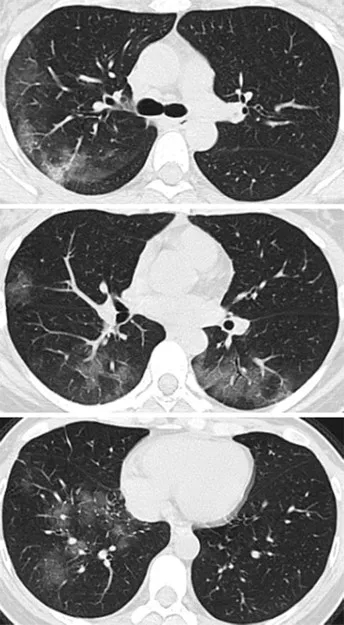

病例2,41岁女性,去了一趟武汉,

回来后,开始发热咳嗽,

4天后,她感觉呼吸困难,

去医院X线胸部拍片,检验血液,

都没有发现有啥异常。

但是CT扫描发现

两侧肺周边出现多处斑片状毛玻璃样显影。

图片来自《Radiology》杂志